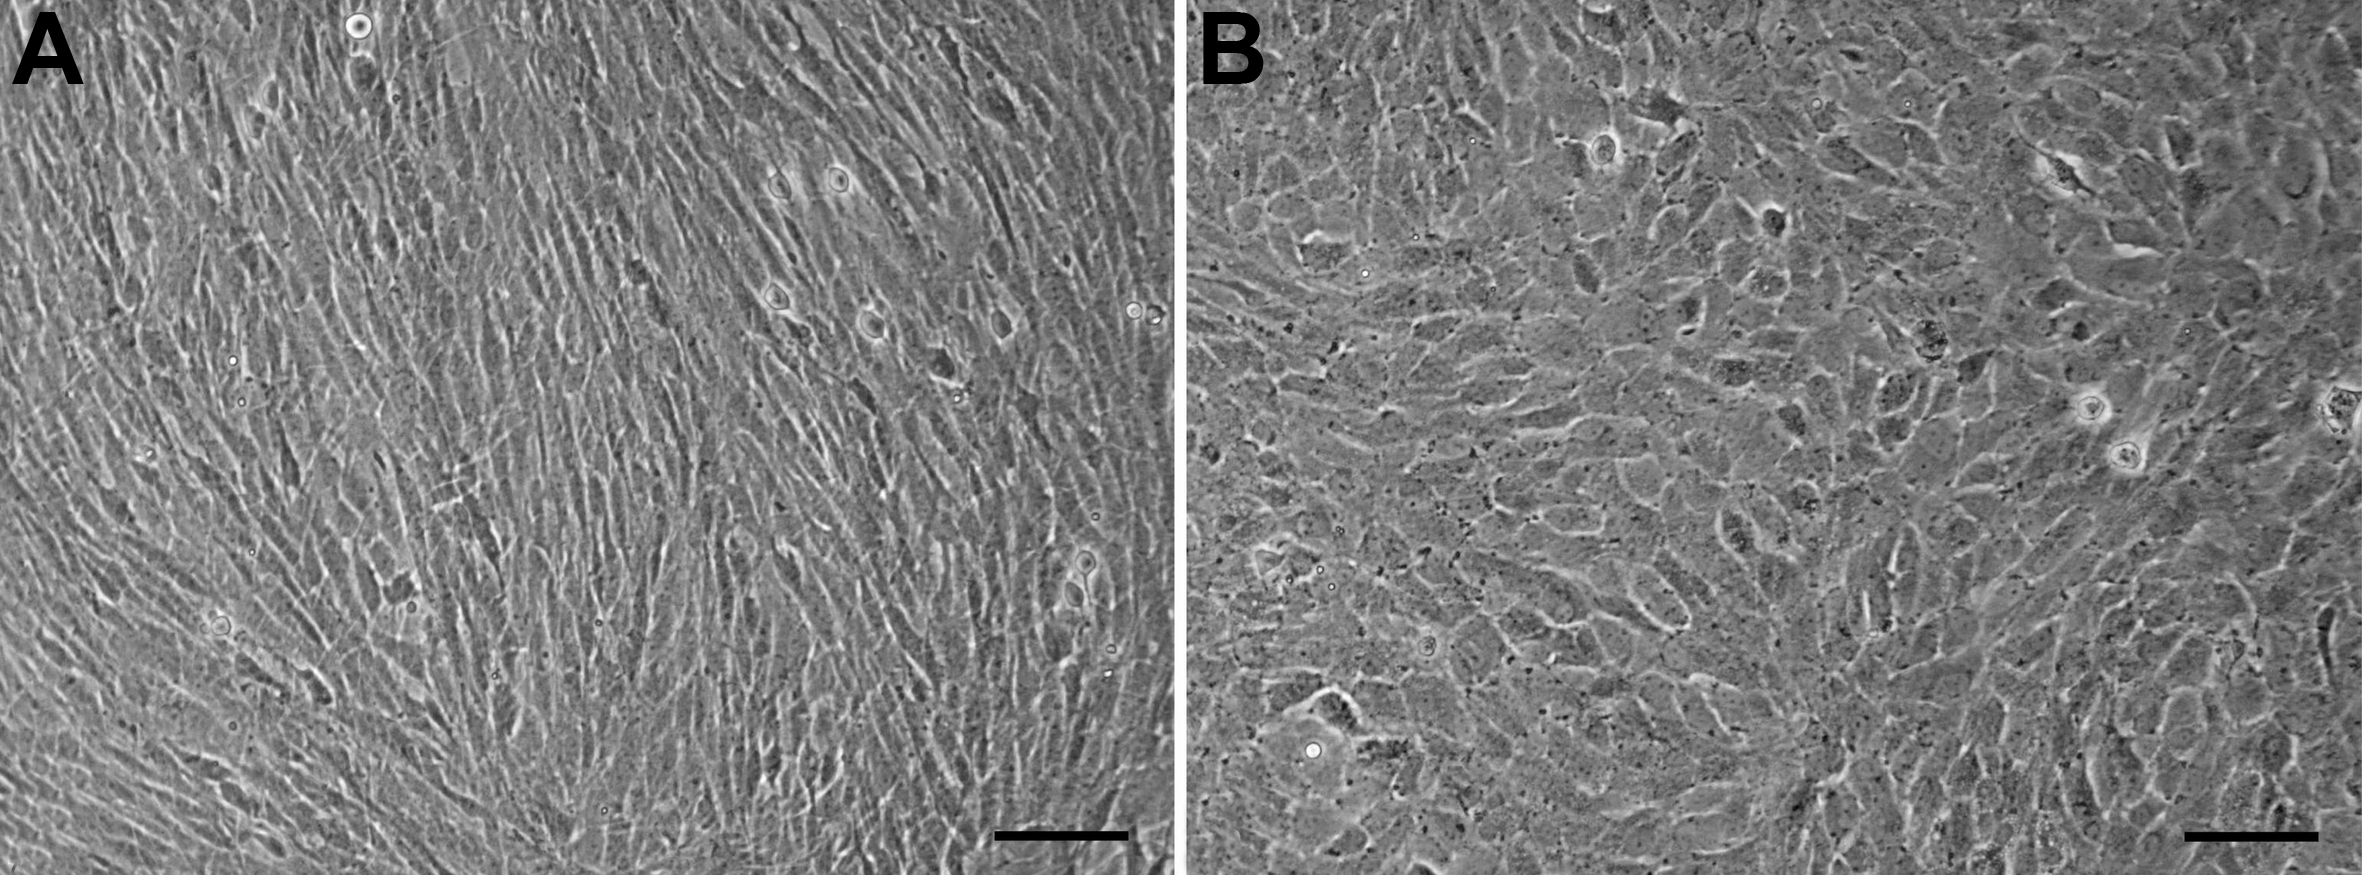

Figure 4. Morphology recovery of HCE cells

at passage 101. A: Control HCE cells cultured in 20%

FBS-containing DMEM/F12 (1:1) medium, showing the fibroblastic

morphology. B: HCE cells cultured in 5% BCS-containing MEM

medium, showing the more corneal endotheloid-like morphology. Scale

bar: 50 μm.